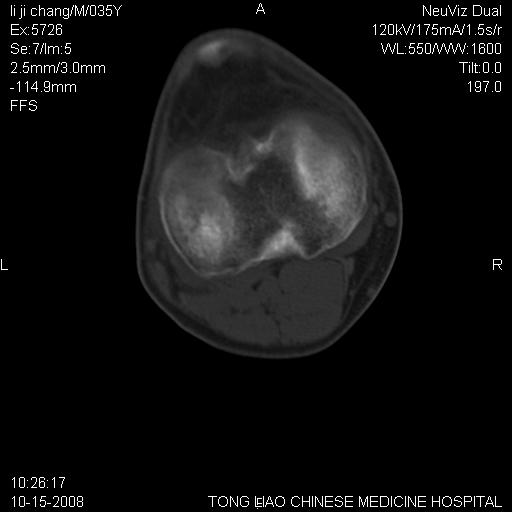

男,35岁,骨科诊断骨性关节炎。继往使用过激素,现股骨头坏死。膝关节病变,请会诊

一元论-----亦考虑为坏死

支持考虑无菌坏死

支持无菌坏死伴退行性骨关节病.

剥脱性骨软骨炎:是一种关节下软骨及软骨下骨缺血性坏死。

支持 无菌性坏死伴退行性骨关节病。

支持无菌坏死伴退行性骨关节病